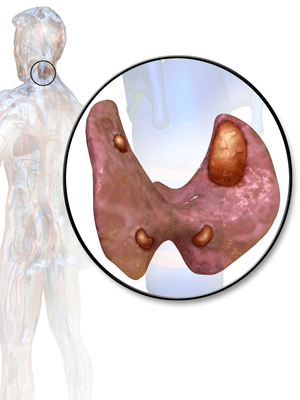

Thyroid and parathyroid.

Primary hyperparathyroidism in 80% of cases is due to a single benign tumor known as a parathyroid adenoma with most of the rest of the cases due to a multiple benign tumors.[4][2] Rarely it may be due to parathyroid cancer.[4] Secondary hyperparathyroidism typically occurs due to vitamin D deficiency, chronic kidney disease, or other causes of low blood calcium.[2] Diagnosis of primary disease is by finding a high blood calcium and high PTH levels.[4]